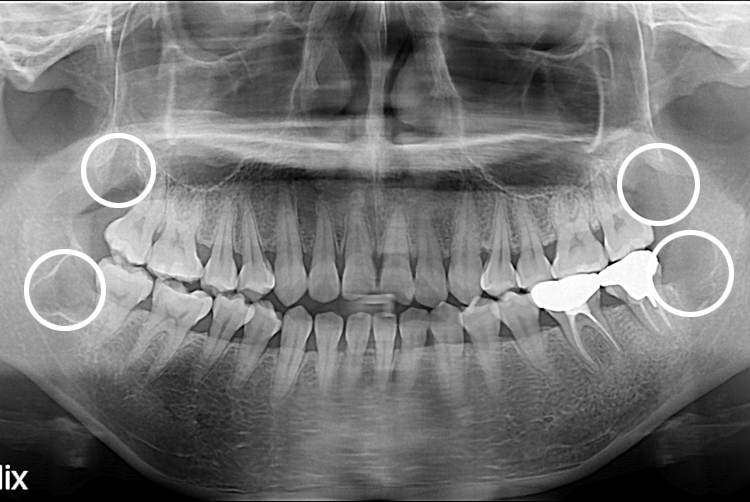

[사랑니] 완전매복 사랑니 발치

치료후 : 2016-07-18

세종치과는 구강악안면외과학 박사이신 원장님이 발치하는 치과입니다.